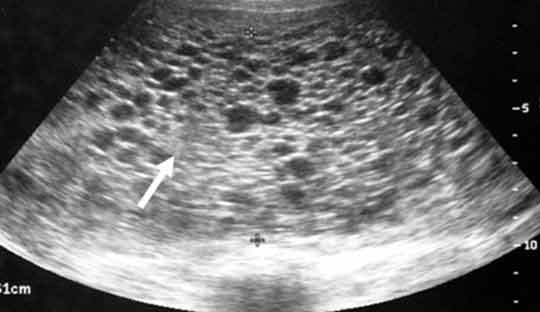

The gestational trophoblastic disorder is rare. Know the possibilities. Cells expand and surround the fertilized egg during normal pregnancy, attaching the egg to the wall of the uterus, and forming the placenta, which is responsible for feeding the fetus during pregnancy. Gestational trophoblastic disease (GTD) is a rare condition— which accounts for less than 1% of all gynecological cancers and occurs in about one out of every 1,000 in the US. If trophoblast cells shift and form a mass in the placenta, this disease occurs after birth, preventing the development of a healthy fetus. While GTD is not usually cancerous, some tumors may get cancerous and spread. GTD is treatable, especially if it is caught early.